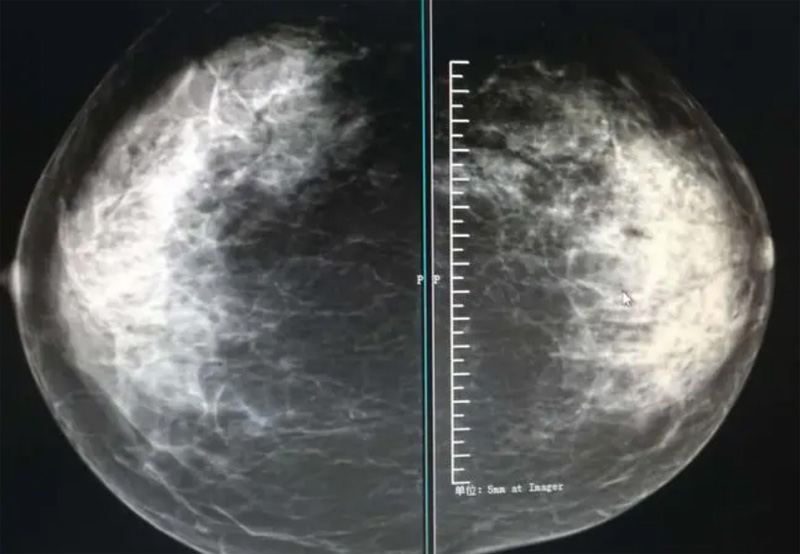

乳腺DR攝影體位有頭尾位及內(nèi)外側(cè)斜位,

乳房在片子的中央,乳頭切線位,可見小部分胸大肌,內(nèi)側(cè)乳腺組織應(yīng)全部包括在片中,外側(cè)乳腺組織盡可能包括在片中。一張好的MLO位圖像顯示如下:乳房被推向前上,乳腺實(shí)質(zhì)充分展開,胸大肌可見,較松弛,下緣達(dá)到乳頭水平,乳頭在切線位,部分腹壁包括在片中,但與下部乳腺分開,絕大部分乳腺實(shí)質(zhì)顯示在片中。乳腺組織外緣可見乳頭的輪廓;乳腺后方的脂肪組織被很好地顯示出來,乳房無皺褶。對(duì)于CC位及MLO位顯示不良或未包全的乳腺實(shí)質(zhì),可以根據(jù)病灶位置的不同選擇以下體位:外內(nèi)側(cè)位(LM)、內(nèi)外側(cè)位(ML)、內(nèi)側(cè)頭尾軸位(MCC)、外側(cè)頭尾軸位(LCC),尾葉位(CLEO)及乳溝位。在臨床實(shí)踐中,對(duì)于常規(guī)體位上發(fā)現(xiàn)的異常改變,可以進(jìn)一步采取一些特殊的攝影技術(shù),包括局部加壓攝影、放大攝影或局部加壓放大攝影技術(shù)。

2、規(guī)范觀圖程序:屏幕軟閱讀或在專用日光觀片燈下膠片閱讀,后者應(yīng)同時(shí)準(zhǔn)備白熾強(qiáng)光燈及觀片放大鏡。注意雙側(cè)乳腺配對(duì)觀察,推薦雙眼橫向掃描,進(jìn)行雙乳相同部位圖像比較分析。

3、乳腺實(shí)質(zhì)背景的確定:觀察乳腺實(shí)質(zhì)與脂肪的構(gòu)成比例,了解乳腺實(shí)質(zhì)類型,以判斷對(duì)某些乳腺攝影征象敏感性的影響,有利于確定乳腺攝影對(duì)疾病的診斷價(jià)值。